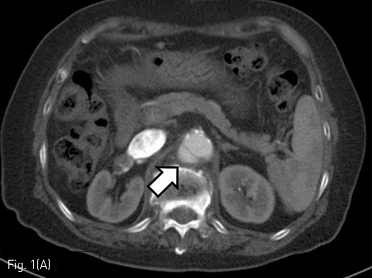

시술 3개월후 시행한 조영증강 CT와 혈관조영 영상에서 복부동맥류의 크기는 0.9 x 1.4 cm으로 줄어들었다. 복강 동맥, 상장간막동맥 그리고 양측 신장동맥의혈류는 잘 유지되어 있었다 (Fig. 3). 시술 6개월 뒤 시행한 조영증강 CT에서는 복부 동맥류의 크기가 더 줄어들어 최대 직경 0.5 cm으로 측정되었다(Fig. 4).

Fig 4

6-month follow up CT shows near-complete thrombosis of the saccular aneurysm (arrow).